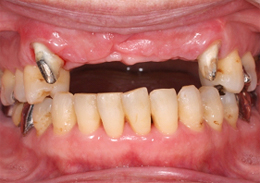

ボーングラフトインプラント(ブロック骨移植をし骨造成をしたインプラント)

ボーングラフトは、十分な量の骨が得られない場合に、骨をブロックで切り出し、移植することで必要な骨を作り出します。

- 主訴

- 上顎前歯の噛む時の痛み

- 治療内容

- 上顎前歯部を抜歯すると大きな骨吸収を予測したため、下顎臼後三角部より骨片を採取し、抜歯時にインプラント埋入と同時に骨造成を行なった

- 治療費用

- 800,000円(税別)

- 治療期間

- 5ヶ月